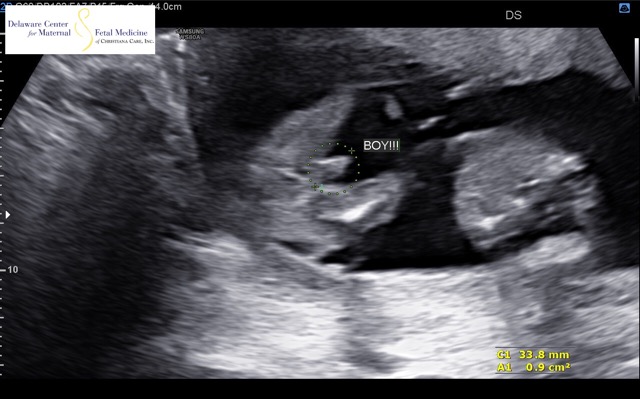

Our identical twins are.....BOYS😍💙💙

Almost 17 weeks along and today we found out our identical twins are boys 😍💙👶🏼💙👶🏼.. I’m so in love and so excited.💙 first time mom here!!